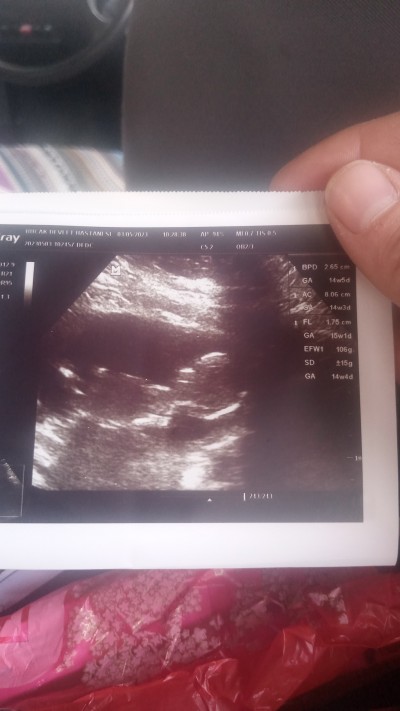

Kızlar 15 haftaya girdim doktor cinsiyet erkek görüyorum yüzde yüz diyemem ama erkek görüyorum dedi 3 hafta sonra netlesir dedi ultrason resmide verdi sizce tahmini doğru mudur?

Gebelik haftası 15 hafta